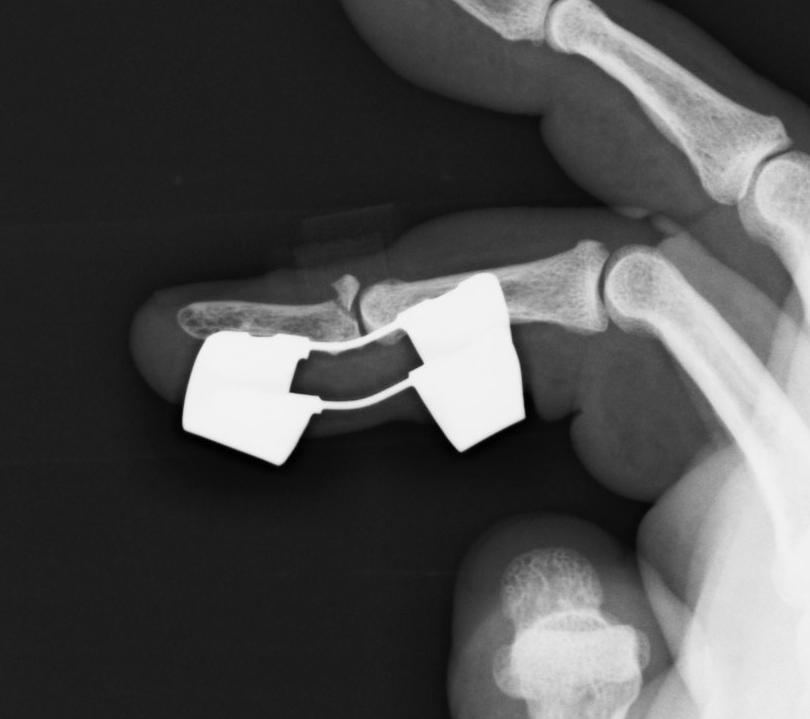

骨折が少し転位して癒合が遅れているため直前まで走るかどうか迷いました。天気予報も曇時々雨だったので雨だったら止めようと思っていました。しかし何とか天気も持ちそうだということで走る事にしました。手袋を縦に切って装具のまま指を入れて絆創膏で固定して走りました。 強く握ると少し痛みが出る程度です。あまりタイムは期待できないのでリアシートも外さずガソリンも満タンで走りました。気合いが入らないのでレーシングスーツも着ませんでした。天候は曇で気温は12度〜13度ととても良い条件でした。